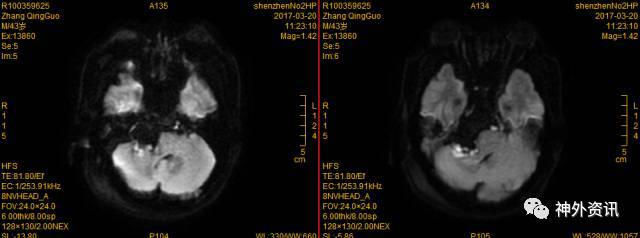

4. 术前影像学检查如下:

右桥小脑角区可见不规则形异常信号肿块,边界清晰,密度尚均匀,范围约6.8*5.9*5.8cm,病灶沿间隙匍匐生长,呈长T1长T2信号改变,DWI呈高信号,增强扫描未见明显强化,与周围组织分界清,基底动脉受压向左侧移位,中脑导水管,脑干、小脑、第四脑室受压变窄,第三脑室、双侧侧脑室扩张积液导。

术后72小时MRI

示手术切除完全